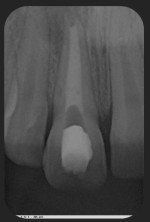

La endodoncia es el último tratamiento odontológico conservador que permite salvar un diente, premolar o molar evitando su extracción. Dicho tratamiento se basa concretamente en la eliminación de la pulpa ( nervio, vena y arteria recubiertos de una membrana, que da vitalidad a la estructura interna del diente). Esta pulpa se encuentra en el interior de la cámara y de los de los conductos radiculares o raíces del diente. Una vez eliminada la pulpa y desinfectados los canales o conductos radiculares, se procederá al sellado de dichos espacios vacíos con diferentes materiales inertes ( gutapercha y cementos selladores), evitando así posibles infecciones del tejido óseo. De hecho, la endodoncia es uno de los tratamientos más realizados en las consultas dentales.

Cuando un diente erupciona tiene formadas dos terceras partes de la raíz y no se completa su cierre hasta dos o tres años después de haber erupcionado. La apicoformación es el tratamiento de un diente inmaduro (sin formación completa de la raíz) en estado necrótico, es decir, con afectación del nervio, debido a una causa traumática o caries, motivo por el cual ha detenido el proceso de formación y cierre natural de su raíz.

El tratamiento consiste en limpiar el nervio hasta el final de la raíz formada y rellenarlo con hidróxido de calcio. Con esto conseguimos eliminar la infección y además poder ir, en período de 2-3 meses, limpiando este material y rellenando de nuevo hasta el final nuevo de raíz formada.

Una vez el diente esté maduro (raíz completa) se procederá al sellado del canal del nervio con material definitivo. Este último paso es el mismo que realizamos en una endodoncia, que es el tratamiento del nervio en un diente maduro. Durante todo el proceso se irán realizando controles radiográficos.